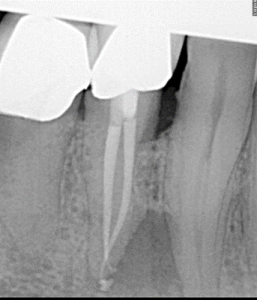

Root Canal / Retreatment

Clinical Cases